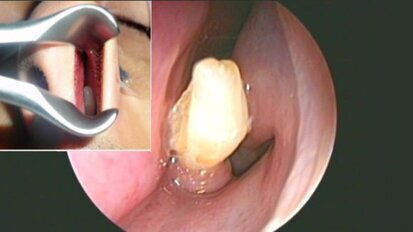

Сляп човек възвърна зрението си благодарение на протеза, направена от корен на зъб

Най-честите причини за увреждане или загуба на зрението са потъмняване на роговицата...